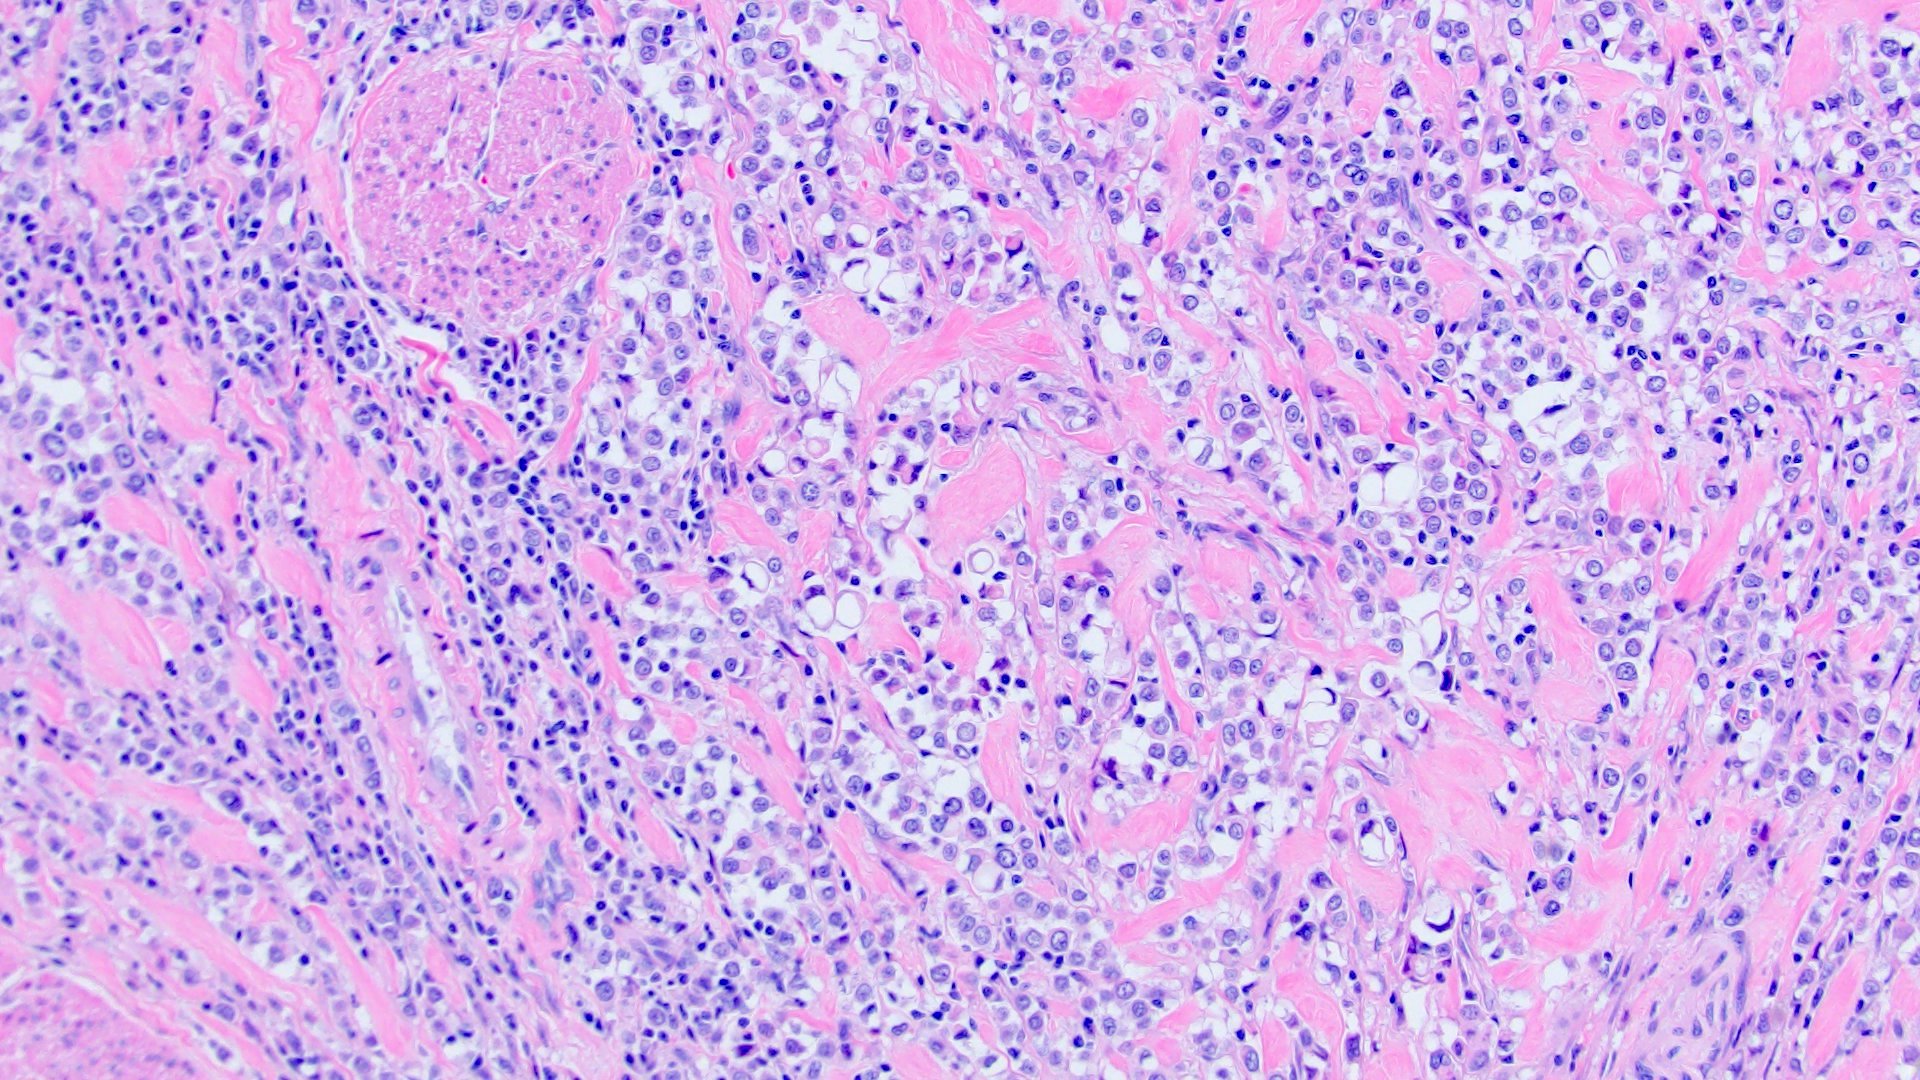

Microscopic (histologic) description

- Discohesive single cells with eccentrically placed nuclei and abundant eosinophilic cytoplasm

- Often deeply infiltrative but with minimal stromal reaction (Eur Urol Focus 2020;6:653)

- Further subclassified into classic, pleomorphic and desmoplastic subtypes:

- Classic: signet ring-like morphology, singly scattered and discohesive in loose aggregates forming cords (Hum Pathol 2019;90:27)

- Pleomorphic: similar to classic but with pleomorphic nuclei and more atypia; can be rhabdoid and bizarre appearing (Hum Pathol 2019;90:27)

- Desmoplastic: plasmacytoid neoplastic cells with a surrounding desmoplastic stromal response (Hum Pathol 2019;90:27)

- Associated with sarcomatoid variant in 31% of cases (Hum Pathol 2019;90:27)

- Often mixed with other histologic subtypes; in 1 case series, 53% of PUC had mixed histologic subtypes (Am J Clin Pathol 2017;147:500)

- Despite resemblance to signet ring carcinoma cells, notably lack extracellular mucin, contrasting to signet ring adenocarcinoma (Acta Cytol 1991;35:277, Am J Surg Pathol 1991;15:569)

Microscopic (histologic) images

Contributed by Timothy Isaac Miller, M.D., M.A., Nicole K. Andeen, M.D. and Maria Tretiakova, M.D., Ph.D.